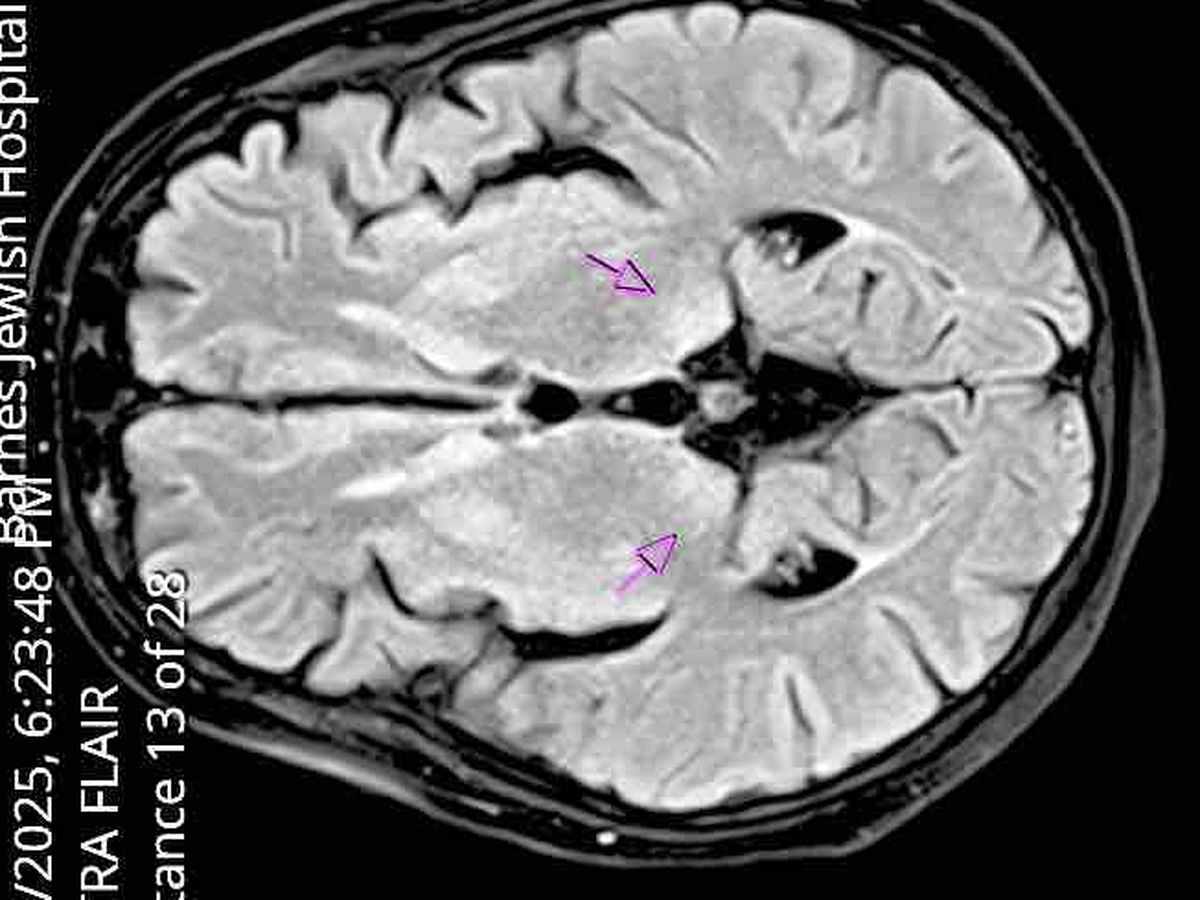

Hello everyone, I wanted to take the time to thank everyone who has already reached out and supported me. Despite working in Non-Profit healthcare, I am terrible at asking for help for myself. With encouragement from a former coworker (Shoutout to Shay Aka Ms. Henderson), I chose to create a GoFundMe as a last resort. On January 3rd, 2025 my Mother came by my apartment to drop off a Christmas present. I had not been answering my personal phone or my work phone (which is unlike my normal self). When I did not answer the door, my mother had my landlord unlock my apartment, where I was found on the floor unconscious and eventually confabulating while unable to walk. My mother called 911 and I was rushed to the hospital and quickly admitted. My mother believes I was unconscious and alone for several weeks and the hospital treated and kept me for two weeks. I have little memory of what happened, but I remember having extreme back pain and not being able to walk. On the 8th day in the hospital I felt like I had finally, "woken up" and asked where I was and what happened. I was informed that I was diagnosed with encephalopathy and Wernicke's Korsakoff Syndrome from vitamin b-1 deficiency due to past struggles with anorexia, bulimia, and alcoholism. I have no issues with these disorders currently, but the damage I caused to my body from past poor coping skills and overworking myself, made my condition irreversible. I currently attend physical therapy, occupational therapy, see a nutritionist, go to memory care, neurology, and psychiatry appointments. I am in the final stages for approval for disability due to short term memory loss, ataxic gait (unable to walk without a walker, reach high or low places, lift small amounts of weight, etc.), horizontal nystagmus, CSF spaces (Cerebrospinal Fluid spaces within the cavities of the brain and spinal cord), inability to drive, shower, cook, dress, take my dog outside, do laundry, climb stairs, and remember which medications I have or have not taken independently. I struggle to put on clothing, shoes, I leave the gas on or burn and break items if I attempt to do things on my own. I am currently rated within the 11% of high risk elderly patients at my physical therapy office. I fall often and run into objects with my walker and receive help from my sister and mother. However, there is not much assistance currently for single women my age who are not married and without children. I had a large savings, from the last two years with the Hopewell Center, that I used to pay my rent until recently. I am currently on step 3 of 5 for disability due to switching insurance plans and delays from my name being spelled wrong, my memory loss causing me to fill out documents improperly, and waitlists for treatment since January of 2025. I hope to continue to be an inspiration and to help others to the best of my ability, but my savings have run out and my grandmother has helped me for a large portion of my recent finances. I know so many people are struggling, and I hate asking for handouts. If anyone would like to donate $1 towards my rent this month or message me to Zelle my landlord Celia Fang. I would be happy to help anyone with any psychiatric healthcare, community resources/needs, guidance. May God bless you all and thank you for your time and prayers.